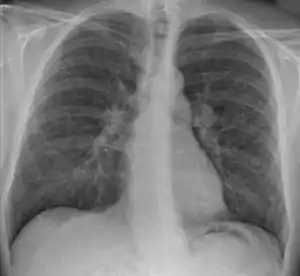

Hilar adenopathy especially on the person's left (AP CXR)

Hilar adenopathy especially on the person's left (lateral CXR)